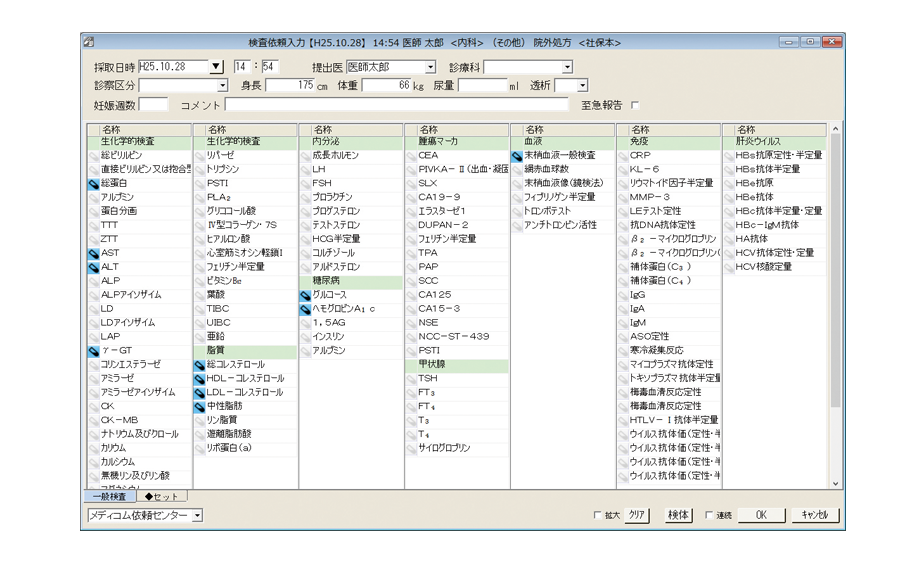

ワンタッチセット入力

ワンタッチボタンを指でタップするだけで、よく使う所見や処方などをかんたんに入力できます。

ワンタッチボタンは自由に設定できるので、診療内容を入力する際に必要なものを任意に登録できます。入力は指だけではなく、ペンタッチでもマウスクリックでも可能です。